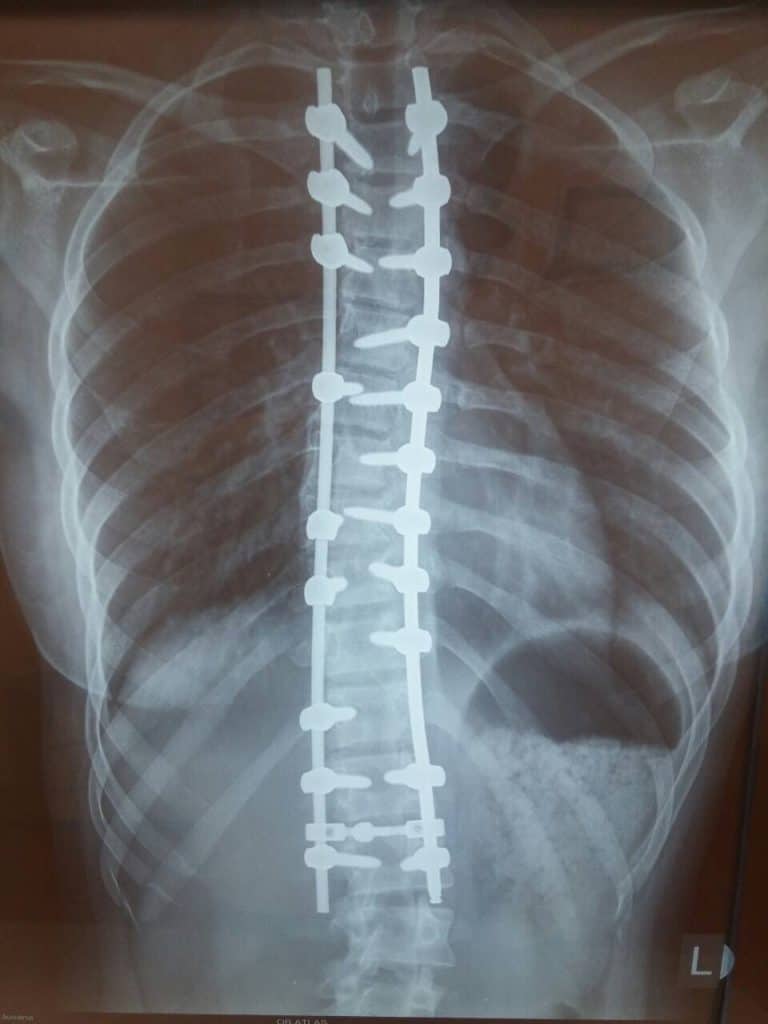

الجنف بعد الجراحة

قام الفريق الطبي لجراحي العظام وجراحي الأعصاب في مستشفى أطلس العام ، لأول مرة في صربيا ، بإجراء عملية تنظيرية كاملة لتشوه العمود الفقري الذي يعد في الوقت الحالي الطريقة الأكثر تقدمًا للعلاج الجراحي في العالم.